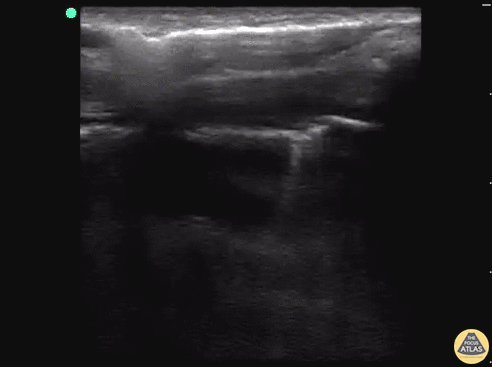

Een klinische setting waarbij POCUS zeer goed toegepast kan worden is de verdenking pneumothorax. Een van de kenmerken van een pneumothorax is de afwezigheid van lungsliding (zie: de basisprincipes van longechografie).

Lungsliding is een fysiologisch verschijnsel. De pleura pariëtale en viscerale bewegen tijdens de ademhaling ten opzichte van elkaar (zie video 1a). Bij een pneumothorax is de lungsliding afwezig doordat de pleura juist niet meer tegen elkaar aan liggen (zie video1b). Bedenk hierbij goed dat er nog allerlei andere oorzaken kunnen zijn als oorzaak van de afwezige lungsliding!

Video 1a. Lungsliding.

Video 1b. Geen lungsliding.